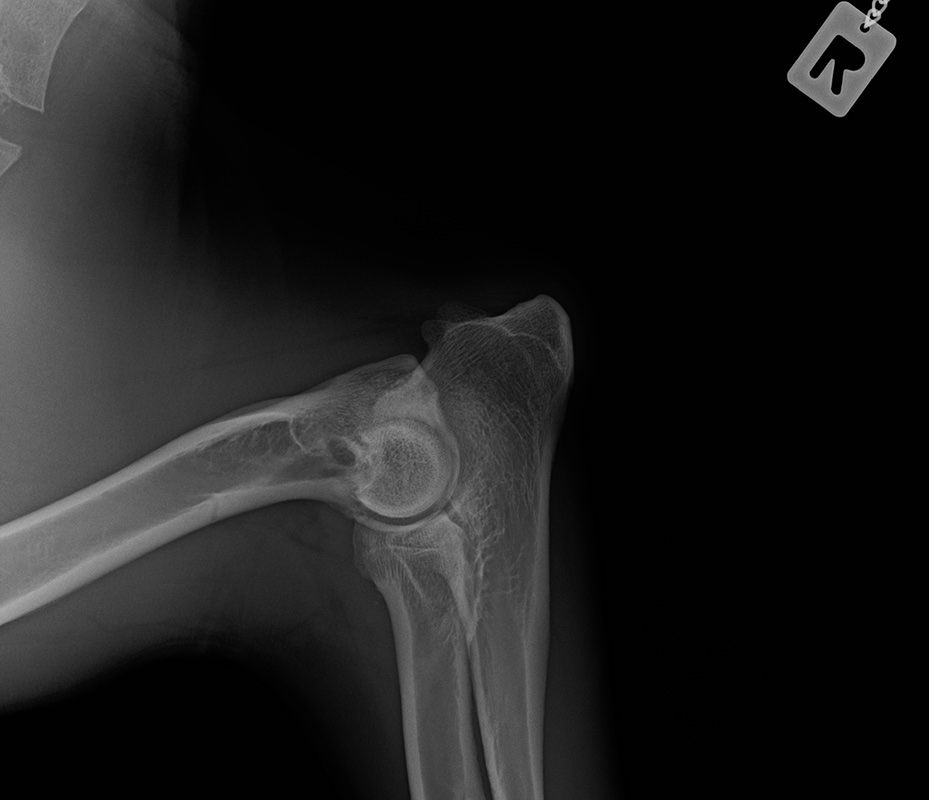

Wir warten jetzt mal die offizielle Auswertung ab. Bin auch gespannt, was nun bei OCD und Lendenübergangswirbel rauskommt. Und welcher LÜW-Typ.

Das ist ganz einfach. Man schreibt ne Email, bittet um ein Privatgutachten und schickt ihm die Röntgenbilder.

Das Ergebnis + Rechnung kommt echt schnell ( 1-2 Tage)